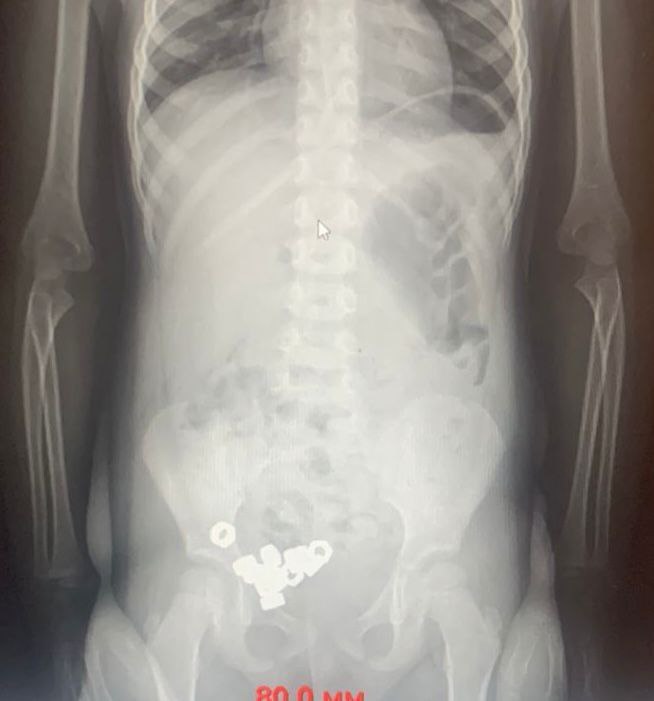

В Воронеже малыш проглотил 16 гаек

Родители трехлетнего мальчика обратились к врачам. Они предполагали, что ребенок проглотил инородные предметы. На момент осмотра симптомов не было. Однако на рентгене заметили в животе 16 маленьких гаек.

Врачи назначили диету. На третий день все инородные тела успешно вышли естественным путем, и ребенка выписали.